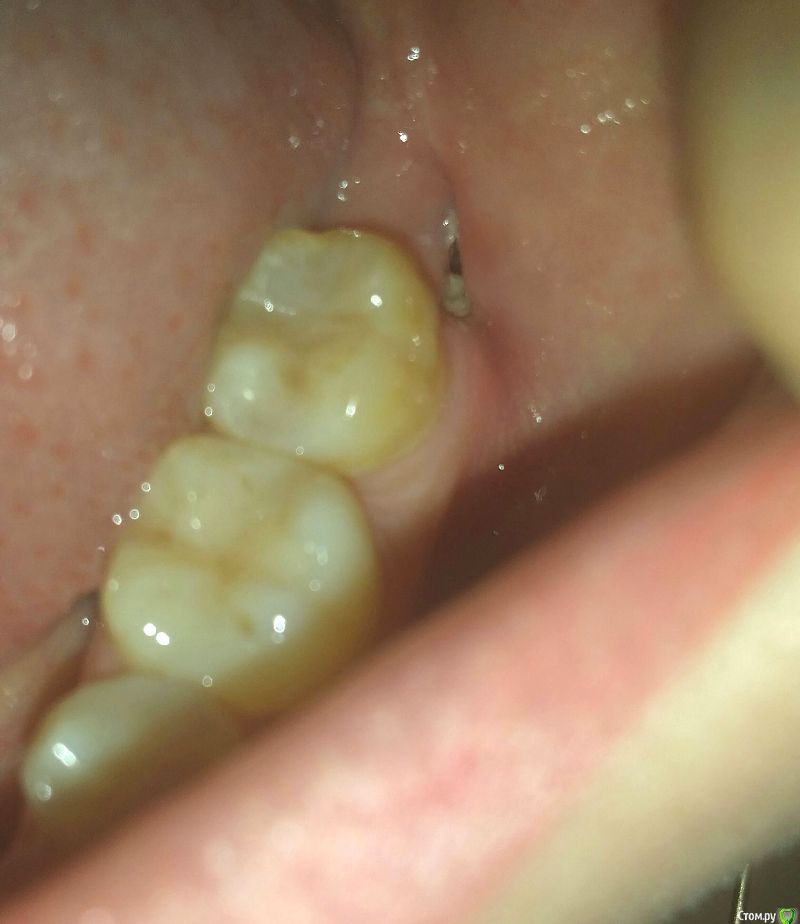

Alena.vsk Опубликовано 2 августа, 2016 Автор Поделиться Опубликовано 2 августа, 2016 (изменено) Добрый вечер, уважаемые хирурги! Если сможете, ответьте пожалуйста еще на один вопрос. После удаления зуба сгусток не образовался - крови не было, поэтому доктор заложил на 3 дня йодную штуку.Наложил два шва,я так понимаю стянул края лунки, но не зашил наглухо. Первые три недели 1-2 раза в неделю доктор промывал лунку длинным шприцом и закладывал в лунку какое-то рассасывающееся мятное вкусное лекарство, чтобы пища не попадалаПоследний раз я была у него 10 дней назад, и т.к. он уехал - в следующий раз попаду к нему только через пару недель. Беспокоит щель у лунки, я так понимаю что она хоть и маленькая, но внутри за десной по прежнему все еще большая полость. И очень переживаю что туда будет набиваться еда, которую обычным полосканием никак не вымыть, т.к. щель узкая.Жую до сих пор только на здоровой стороне. Лекарство рассосалось дня 3 назад, получается щель теперь открыта. Вот так это выглядит (фото), если щеку слегка оттянуть пальцем. Сегодня не выдержала, и аккуратно убрала белое скраю - зубочисткой (убралось легко, явно пища). Собственно, вопрос: можно ли как то ухаживать за этой лункой до приезда врача, чтобы полость не забилась и не воспалилась за две недели?Была мысль купить обычный шприц, и без иглы промывать хлоргекседином под напором, но боюсь навредить. И, сколько нужно времени в среднем, чтобы затянулась лунка с таким зубом как у меня? Или чтобы края десны сраслись в единое целое? Очень уже хочется жевать обеими сторонами.Лунке - месяц. Изменено 2 августа, 2016 пользователем Alena.vsk Ссылка на комментарий